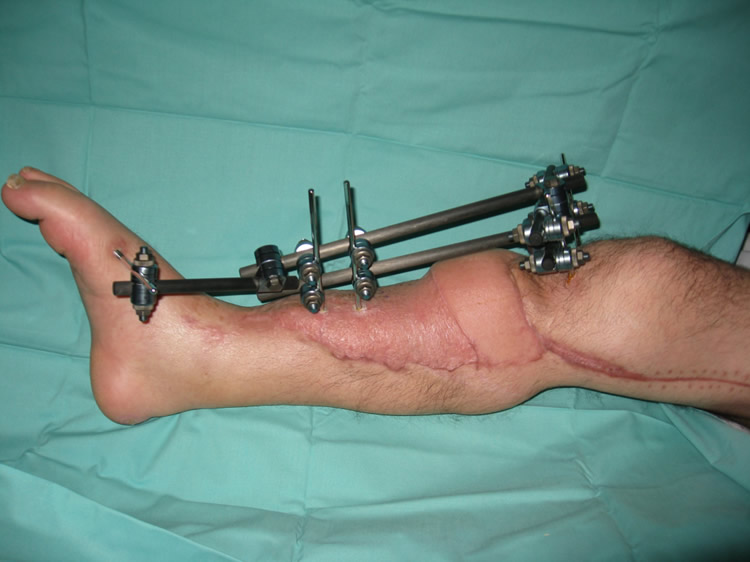

Paso 2: Resección de tejido necrótico y cobertura cutánea definitiva

A los 10 días se resecó la piel y tejidos necróticos. La herida se cubrió con transferencia microvascular de colgajo latissimus dorsi e injertos de piel.